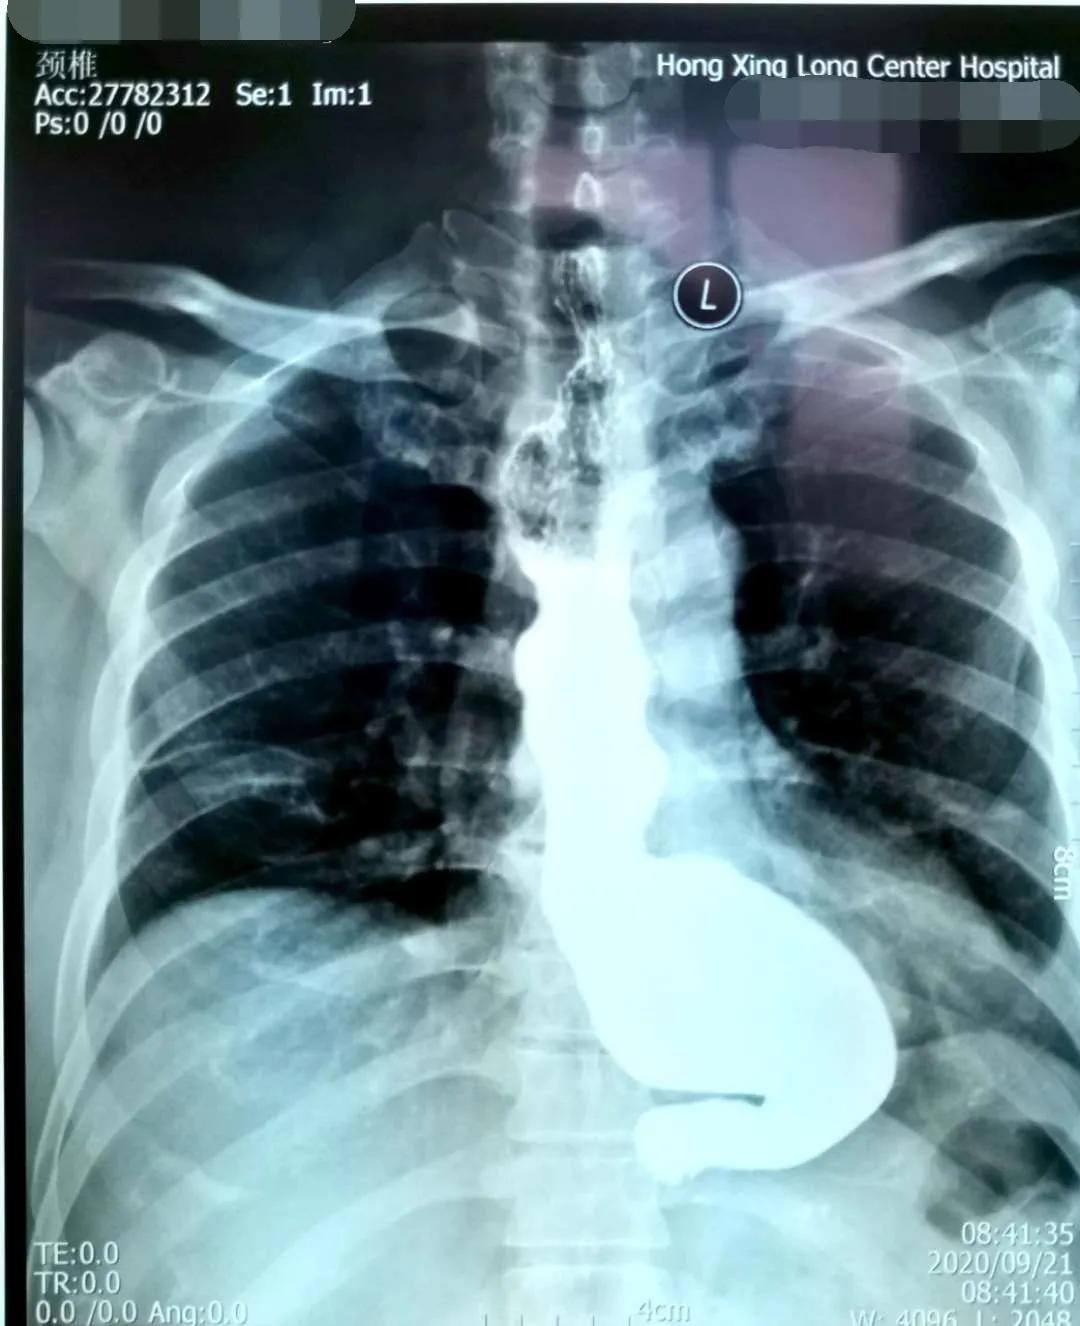

10月7日,红兴隆中心医院成功开展首例内镜下POEM术治疗贲门失弛缓症,填补了红兴隆中心医院空白。

贲门失弛缓症又称贲门痉挛、巨食管,是由于食管神经肌肉功能障碍所致的疾病,临床表现为咽下困难,食物反流和下端胸骨不适,以及因食物反流误吸入气管所致咳嗽,肺部感染等症状。该病治疗不及时,有发生食道癌的风险。

简要病史:患者吕某,男,54岁,因吞咽困难10年余,不能进固体食物,并伴有胸痛,近半年仅能进食流食,来我院诊治。